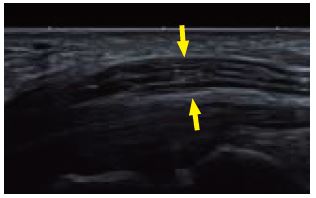

Випадок 1: Серединний нерв

Цей випадок демонструє потовщення правого серединного нерва порівняно з лівим серединним нервом на рівні згинача сітківки, що свідчить про синдром правого карпального каналу.

Використовуючи i24LX8, надвисока частота дозволяє зобразити нейрофібрилярні структури з великою деталізацією і оцінити тонкі осередкові потовщення. Вимірювання підкреслюють

різницю між двома серединними нервами, що підвищує діагностичну достовірність.

a) Поздовжній вигляд серединного нерва демонструє осередкове потовщення (між стрілками)

b) Правий серединний нерв у порівнянні з лівим серединним нервом

c) Правий серединний нерв у порівнянні з лівим серединним нервом з вимірами

Мал. 7.